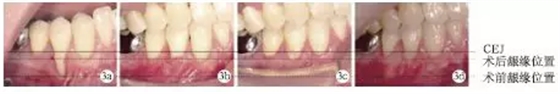

術(shù)前#44頰側(cè)牙齦退縮達(dá)9mm;術(shù)后兩周、術(shù)后兩個(gè)月及術(shù)后1年,頰側(cè)齦退縮減少為2mm,根面覆蓋率為:77.8%,未見(jiàn)進(jìn)行性牙齦退縮(圖3)。

圖3 術(shù)前及術(shù)后根面牙齦覆蓋情況對(duì)比

術(shù)前#44頰側(cè)角化齦寬度極少,小于1mm;術(shù)后2個(gè)月及術(shù)后1年,可見(jiàn)角化齦寬度增加為2mm,且角化齦厚度也明顯增加,見(jiàn)圖4。